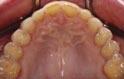

1. What injury can be diagnosed from the teledentistry photo (below), and what is the importance of timely surgery attendance for this type of injury?